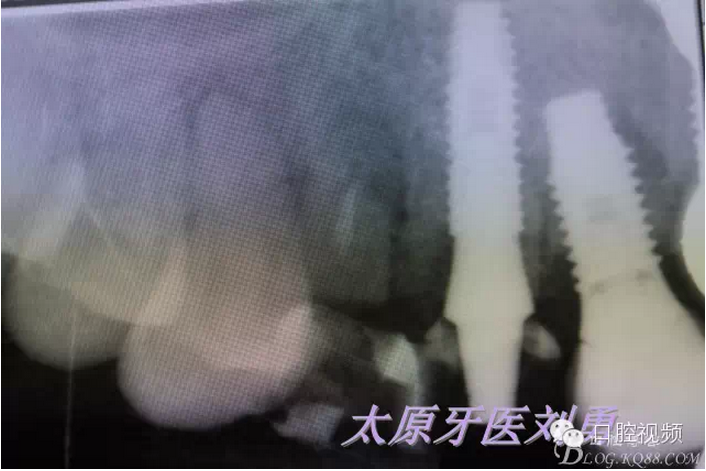

術(shù)后20天,患者A3松動,給予取出種植體,同時探查A3種植窩,可探及周圍骨壁完整,重新制作臨時冠,口內(nèi)檢查A2周圍牙齦健康,給予x片檢查,可見A2種植體周圍正常,A3唇側(cè)根壁可見顯影,并可看到根充物顯影,故考慮A3失敗原因應(yīng)該在于根充物污染導(dǎo)致骨壁感染,因此在以后類似技術(shù)中在拔除腭側(cè)根壁后一定要進(jìn)行X片檢查,排除可能導(dǎo)致失敗的原因。如下圖: